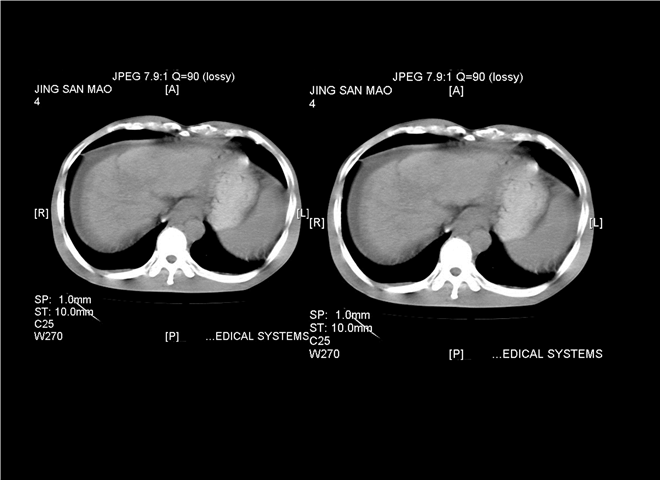

13_CT增强扫描